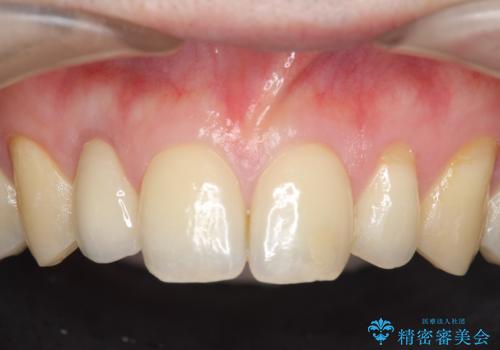

- 金属を使っていない被せ物に替えたいといらっしゃった方の症例です。

再根管治療終了後、オールセラミッククラウンによる補綴を行いました。

今回用いたオールセラミッククラウンはジルコニアフレームという白い素材の上にセラミックを盛っているため、審美性が非常に高いのが特徴です。

また、ジルコニアは人工ダイヤモンドの材料にも使われているほど高い強度を持っており、そのためオールセラミッククラウンは審美性だけでなく、奥歯やブリッジの補綴も可能とするクラウンです。